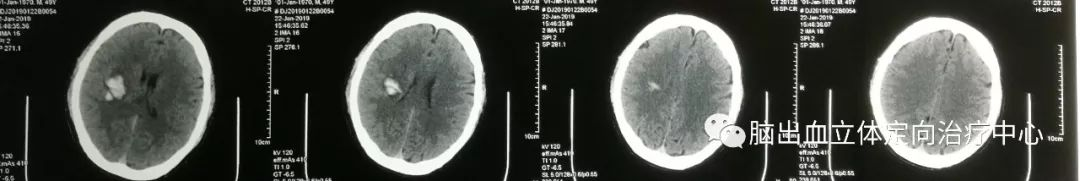

术后14小时CT复查显示血肿量明显减少,病人意识好转、头痛减轻,三脑室显影、侧脑室部分恢复。

发病时CT:

第四天CT:

可见血肿呈分层现象,血肿周围水肿带明显,利用3D测量其各相关CT阈值。

利用3D技术模拟设计穿刺血肿,重建血肿体积约26ml

在3D打印导板下成功穿刺血肿,有约16ml暗褐色不凝血肿液引出,术后应用尿激酶一次,CT复查: